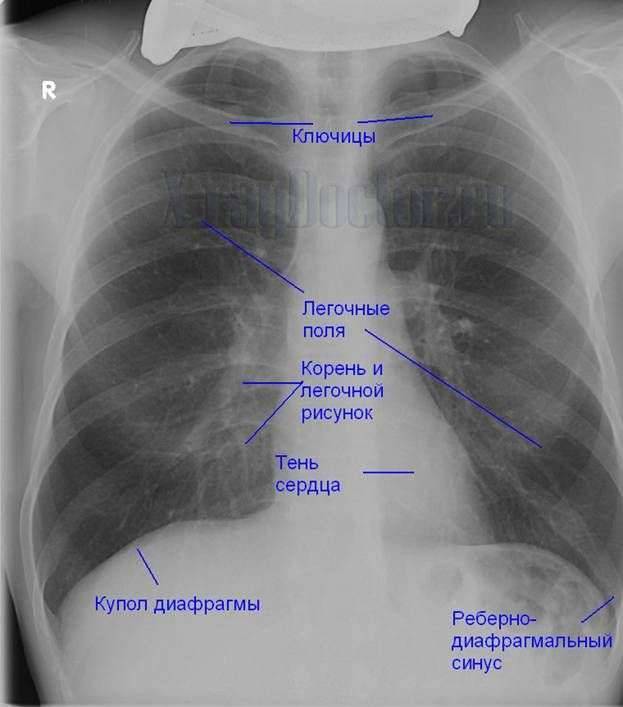

Нормальная рентгенограмма легких: что нужно знать

Раздел: Мудрость в объективе